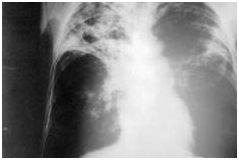

- بیماری سل: عامل این بیماری باکتری Mycobacterium tuberculosis است که به ریه ها حمله کرده وسبب سرفه های همراه با خون می شود. کارشناسان می گویند که یک سوم جمعیت جهان ناقل این باکتری هستند که در 10 تا 5% این افراد عفونت بروز کرده و علائم بیماری در فرد تظاهر پیدا می کند. این بیماری در افرادی که دچار بیماری ایدز هستند بیشتر بروز پیدا می کند. طبق گزارش کارشناسان سازمان بهداشت جهانی ، این بیماری در افرادی که دچار نقص سیستم ایمنی هستد با شدت بیشتر ی بروز پیدا می کند.